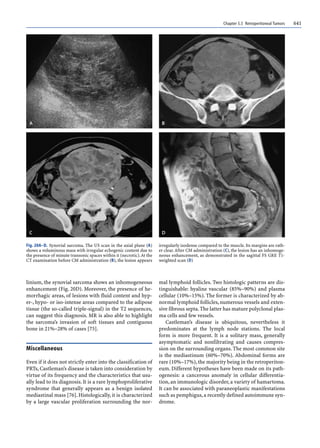

Fig. 6A–D. Giant cell malignant fibrous histiocytoma.At US exam-

ination, the paracoronal scan on the left flank (A) shows a solid

and quite homogeneous mass with a multilobular appearance in

strict contiguity with the spine. At MR examination, in the SE T2-

weighted scan (B), the lesion appears inhomogeneously hyperin-

tense; its medial portion infiltrates the paravertebral muscles and

the spine,invading the canal (arrow).In the T1-weighted scans be-

fore (C) and after (D) CM, the marked vascularization of the mass

is confirmed infiltrating the L2 body and cranially displacing the

left kidney

At imaging, the malignant fibrohistiocytoma is not

easily distinguished from other soft tissue sarcomas.

The combined use of the various methods, especially

MR, together with clinical evaluations, can be useful in

making a differential diagnosis, particularly in the case

of a large lesion that extensively infiltrates the adjacent

structures (Fig. 6).